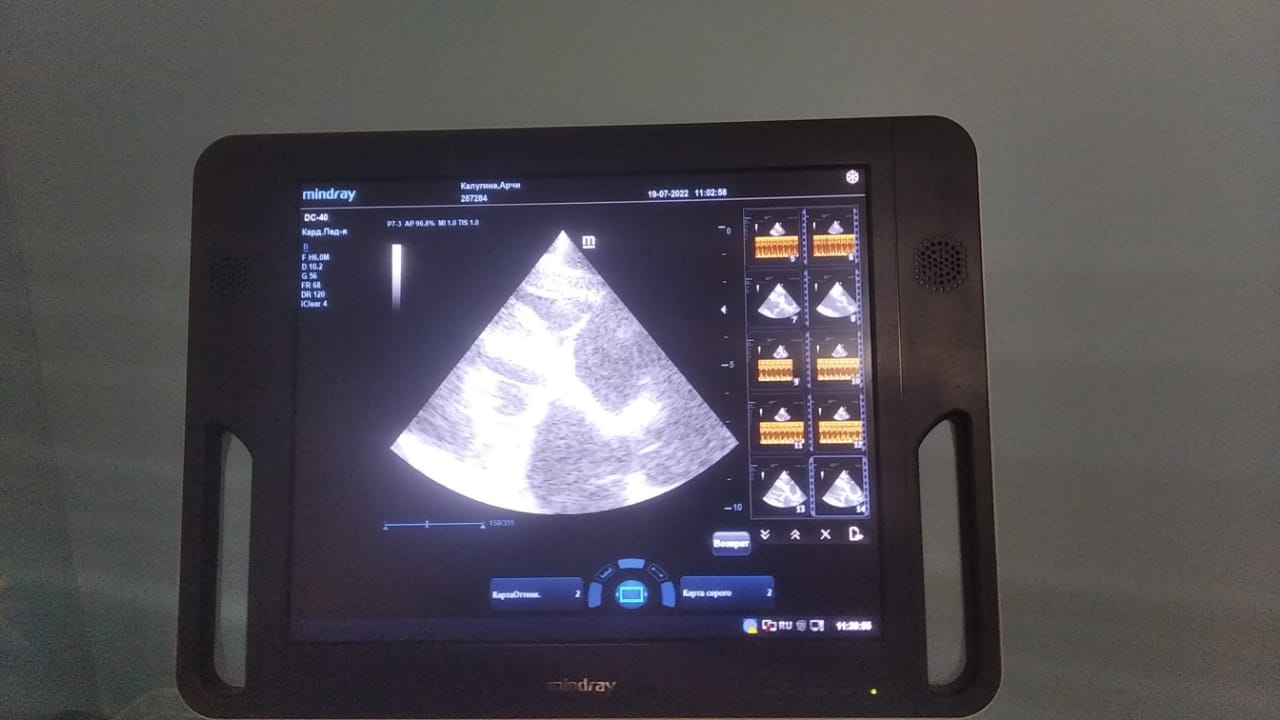

Анализы Арчи. Сердца и легких

Вложения

IMG-20220719-WA0100.jpg

IMG-20220719-WA0102.jpg

IMG-20220719-WA0104.jpg

IMG-20220719-WA0103.jpg

IMG-20220719-WA0105.jpg